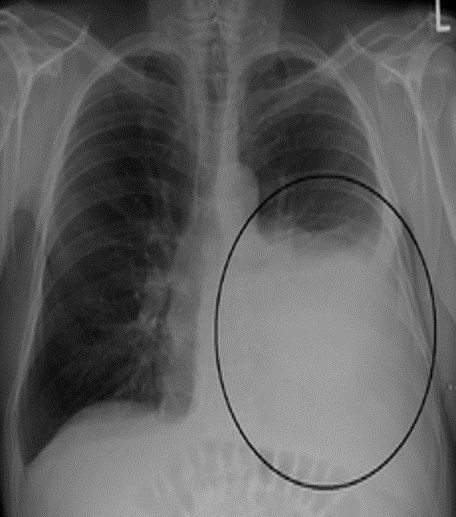

Pleural Effusion

Right sided Pleural Effusion, w/ meniscus sign

Be suspicious of malignancy bc/ large volume